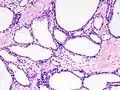

| Micrograph showing a pancreatic serous cystadenoma. H&E stain. | |

Pancreatic serous cystadenoma is a benign tumour of the pancreas.[2] It is usually solitary and found in the body or tail of the pancreas, and may be associated with von Hippel–Lindau syndrome.[2]

Pathologists classify serous cystic neoplasms into two broad groups. Those that are benign, that have not spread to other organs, are designated "serous cystadenoma".[5] Serous cystadenomas can be further sub-typed into microcystic, oligocystic (or macrocystic), solid, mixed serous-endocrine neoplasm, and VHL-associated serous cystic neoplasm. This latter classification scheme is useful because it highlights the range of appearances and the clinical associations of these neoplasms. Serous cystic neoplasms that have spread ("metastasized") to another organ are considered malignant and are designated "serous cystadenocarcinoma".